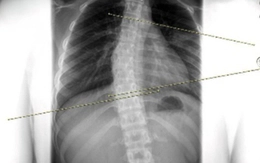

Nam thanh niên 20 tuổi suýt mất mạng vì biến chứng viêm xoang